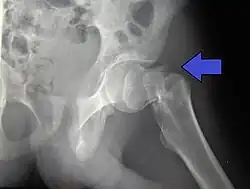

.jpg)

X-rays of the affected hip usually make the diagnosis obvious; AP (anteroposterior) and lateral views should be obtained.